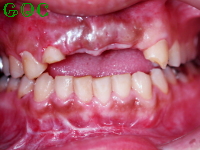

▼前歯を抜いた状態![]() |

南雲先生に診てもらうと事故により前歯を失ってから時間が経過しているために上顎の歯茎が退縮しているとのことでした(事故により歯だけでなく周りの骨も失った)。

その状態ですぐにインプラントを埋め込むと、長い不自然な歯を入れることになってしまうと言われました。歯の見えている部分は骨からの距離であるため、歯を長くしないといけなくなるのです。

そこでまずは骨と歯茎の造成を行いました。

その手術が終わり半年後くらいして落ち着いた段階で、上顎前歯に3本のインプラントを埋め込みました。